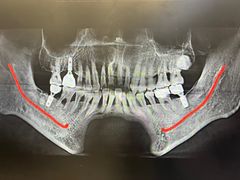

• 牙博士口腔品牌连锁(杨浦店)

• -牙博士口腔品牌连锁(杨浦店)